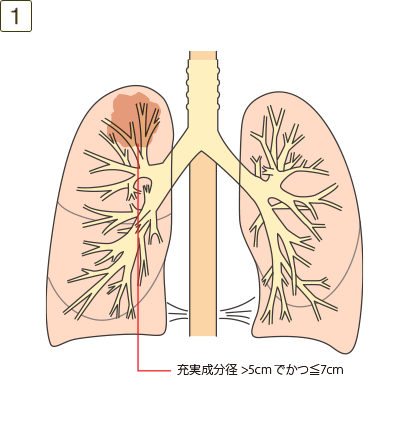

T3

充実成分径>5cmでかつ≦7cm、または充実成分径≦5cmでも以下のいずれかであるもの・壁側胸膜、胸壁(superior sulcus tumor を含む)、横隔神経、心膜のいずれかに直接浸潤・同一葉内の不連続な副腫瘍結節